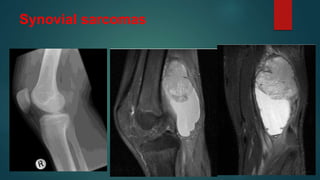

Synovial sarcomas

• #103 Synovial sarcomas are relatively common intermediate-to-high grade malignant soft tissue tumours, often with an initial indolent course, affecting young patients, and most commonly involving the soft tissue surrounding the knees